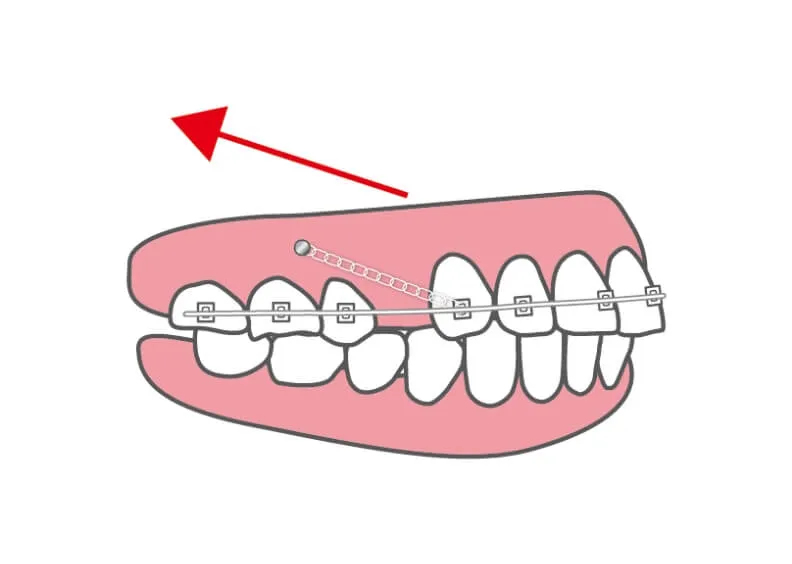

インプラント(アンカースクリュー)矯正|大阪府枚方市の辻村, 歯科矯正用アンカースクリューを用いた 矯正歯科治療クインテッセンス出版先生の臨床を大幅に広げる医療アイテム、それがアンカースクリューである。アンカースクリューを使えば、傾斜した歯のアップライト、対合歯を失ったために挺出した歯や歯列の圧下、残根を利用するための挺出、歯の近遠心方向への移動などのLOT(限局矯正)が簡単にできてしまう。一般臨床医のマストアイテム。本書は、矯正歯科医のエキスパートが一般臨床家のためにアンカースクリューの利用方法をわかりやすく解説している。保田 好隆定価: ¥ 10560(税込)書き込みなし中古品にご理解ある方、よろしくお願いします。

歯科矯正用アンカースクリューを用いた 矯正歯科治療クインテッセンス出版先生の臨床を大幅に広げる医療アイテム、それがアンカースクリューである。アンカースクリューを使えば、傾斜した歯のアップライト、対合歯を失ったために挺出した歯や歯列の圧下、残根を利用するための挺出、歯の近遠心方向への移動などのLOT(限局矯正)が簡単にできてしまう。一般臨床医のマストアイテム。本書は、矯正歯科医のエキスパートが一般臨床家のためにアンカースクリューの利用方法をわかりやすく解説している。保田 好隆定価: ¥ 10560(税込)書き込みなし中古品にご理解ある方、よろしくお願いします。